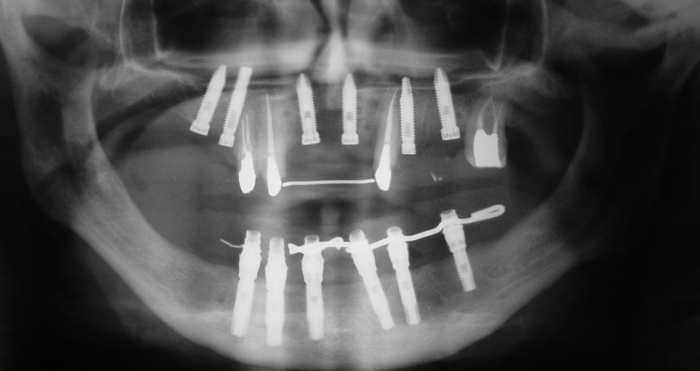

Imagem implantes Superiores em 2009 - Clínica Cliniface

Imagem implantes Superiores em 2009

Prótese Provisória Fixa Inferior em 2009  - Clínica Cliniface

Prótese Provisória Fixa Inferior em 2009

Imagem Próteses Provisórias Fixas Superior e Inferior , em 2011 - Clínica Cliniface

Imagem Próteses Provisórias Fixas Superior e Inferior , em 2011